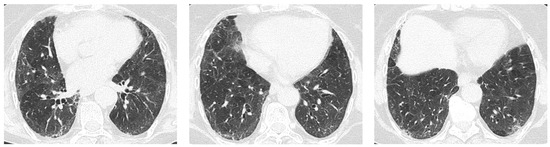

4. Imaging and Histopathology of ILD in pSS

4.1. How Does Radiologic/Histopathologic Pattern Influence the Clinical Picture and Management of pSS-ILD Patients? What Is the Role of Lung Biopsy?